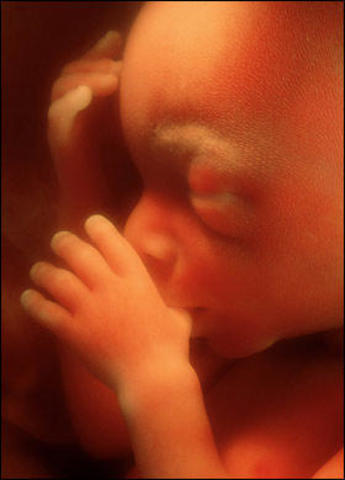

El embrión a formado todos los órganos. Las extremidades ya están formadas. El embrión se mueve y disfruta de todo su espacio dentro del saco amniótico.

Mide 5,5 cm y pesa 9 g. Poco a poco, su cabeza está más erguida y va tomando forma redondeada.

Los ojos, cubiertos por unos finísimos párpados, se van situando en la parte delantera de la cara y sus orejas avanzan hacia su ubicación definitiva.

Las fosas nasales están todavía bastante separadas.

Las cuerdas vocales hacen su aparición.